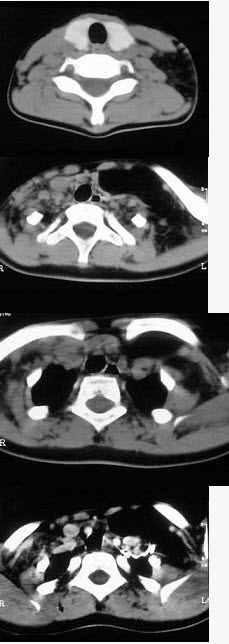

- 单项选择题女,17岁,发现左侧颈部包块半年余,PE://病灶质软,境界不清,无压痛,CT如图所示,应诊断为()。

D、颈部淋巴管瘤